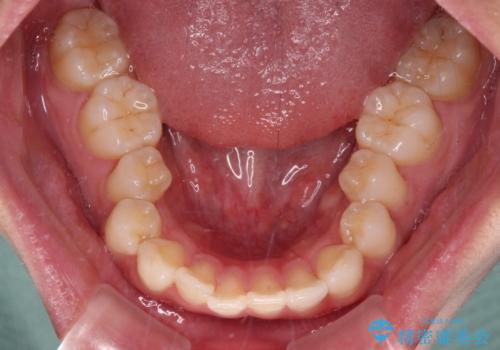

- 全体的なデコボコと口元の突出感を改善したいとのことで来院された患者様です。

このままデコボコを整えるとさらに突出感が増すため、上下左右の第一小臼歯を抜歯し、ワイヤー装置にて矯正しました。